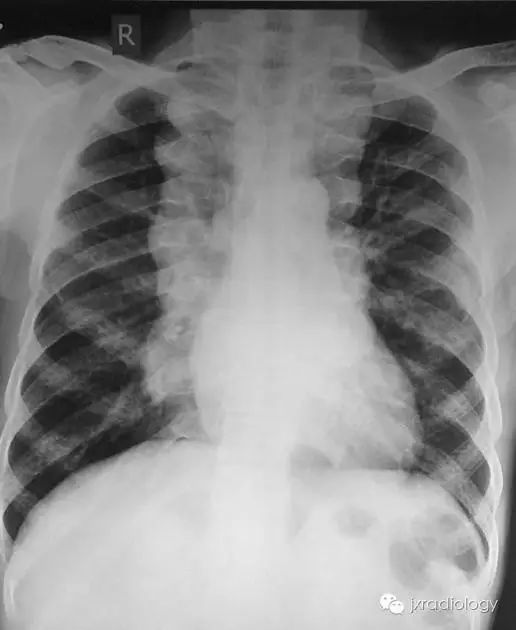

髓外造血器官,影像学上通常表现为器官增大,如超声、CT或MRI上表现为肝肿大、脾大。然而,在不常见的情况下,髓外造血可以发生在胸腔内,呈后纵隔肿块,变现为单侧或双侧脊柱旁肿块,边缘光滑,轮廓分明,常呈分叶状边缘。